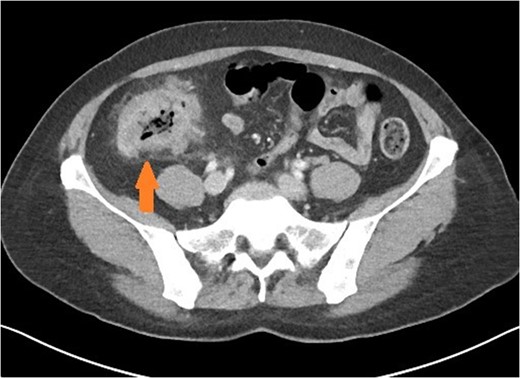

Axial view of patient with caecal carcinoma. Eccentric caecal wall thickening with homogenous contrast enhancement (arrow). Mild pericolic fat stranding is present.

There are a number of CT features that help distinguish bowel wall thickening from malignant and benign causes [3]. A neoplastic cause is suggested if there is focal bowel wall thickening (less than 5 cm of extension) which is typically asymmetrical and eccentric. These may have homogeneous contrast enhancement due to infiltration of a tumour mass, or a heterogeneous areas of low attenuation from ischaemia and necrosis, findings with a sensitivity of up to 97% [4]. Malignancy may also have shouldered edges as opposed to tapering transition to normal bowel wall. Appendiceal dilatation, if present, may be thin walled and without inflammatory stranding due to a gradual obstructive process, although appendicitis can be a presenting symptom for carcinoma. Regional lymphadenopathy and distal metastases, when present, support the diagnosis.